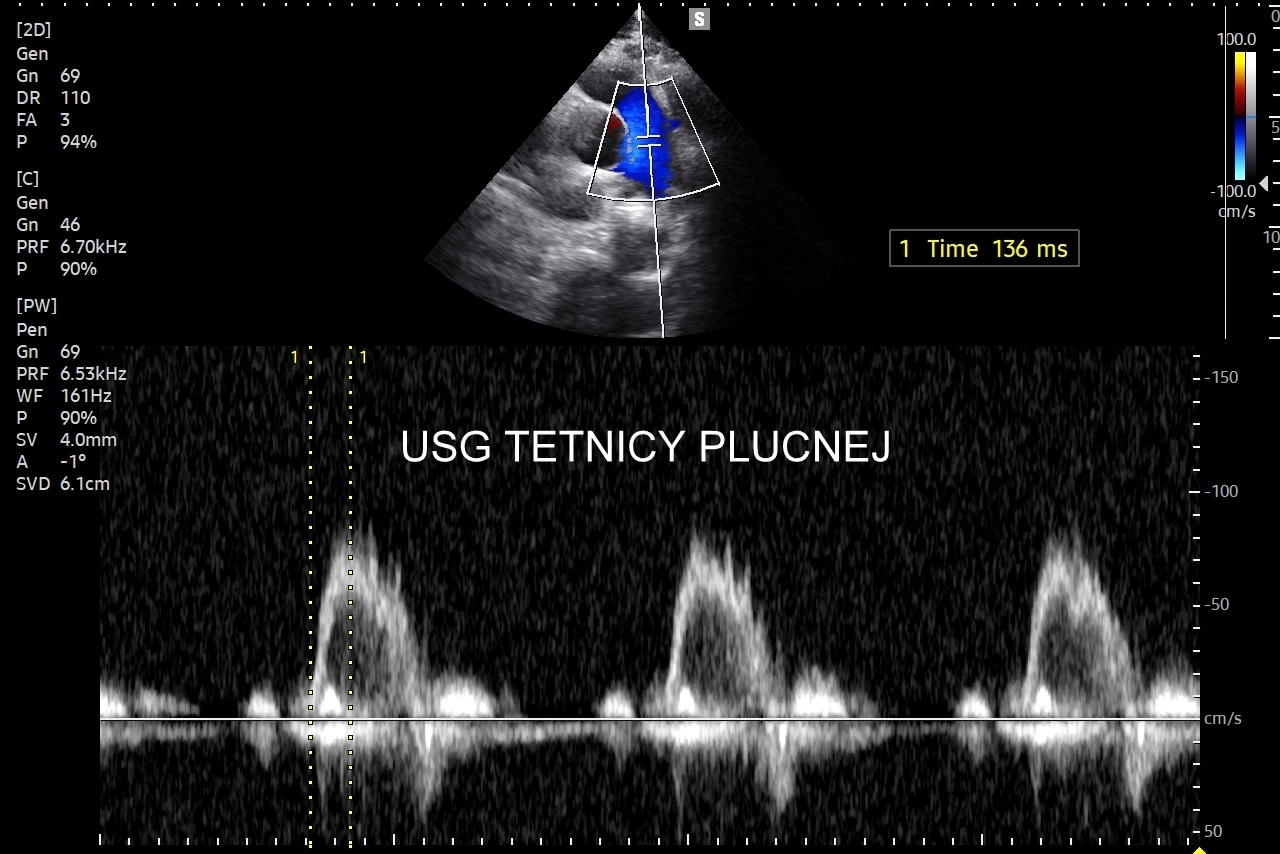

Badanie USG płuc w wybranych przypadkach korzystnie jest połączyć z jednoczesną oceną echokardiograficzną serca oraz dużych naczyń klatki piersiowej, tj. aorty wstępującej i tętnic płucnych. USG układu mięśniowo-szkieletowego klatki piersiowej wykorzystywane jest z kolei w diagnostyce stanów urazowych, takich jak złamanie żeber, czy przeciążenie połączeń chrzęstno-kostnych żeber; w wymienionych przypadkach USG ma wyższą czułość w porównaniu do oceny rentgenowskiej.

Specjalista chorób wewnętrznych. Absolwent Akademii Medycznej we Wrocławiu w 2000 r. Zwolennik nowoczesnych technologii i pionier niestandardowych zastosowań USG w Polsce, w tym użycia obrazowania mikroprzepływów w obrazowaniu płuc, czy badań USG z kontrastem. Na początku lat 2000-ych był jednym z pierwszych lekarzy, który wdrażali szerokie zastosowanie USG w intensywnej terapii. W praktyce ambulatoryjnej wprowadził do regularnego użycia kompleksowe badanie USG klatki piersiowej, płuc i serca. Posiada wieloletni staż kliniczny i szkoleniowy w Polsce oraz zagranicą (Wielka Brytania, Niemcy, Austria, Włochy, Rumunia). Wykonał ponad 40.000 badań USG. Dydaktyk i nauczyciel młodego pokolenia lekarzy w Polsce i Europie.